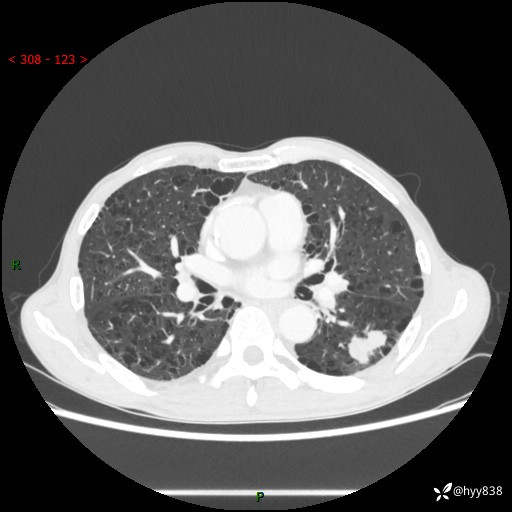

73岁/男,发现肺占位1月余。肺气肿背景,是否恶性倾向---结果公布~

现病史:患者于1月余前无明显诱因出现背部疼痛不适,无明显咳嗽、咳痰、胸闷、咯血、发热等不适,后于2024.5.3至当地市人民医院行胸部CT示:左肺下叶结块,大小约2.2cm*2.6cm,双肺多发小结节,双肺感染性病变,部分纤维增值灶,慢支并双肺局限性肺气肿,肺大泡,纵隔淋巴结增大并部分钙化,冠脉区及大血管壁钙化,双侧胸膜局限性增厚;后口服莫西沙星2周。2024.6.12复查胸部CT示:左肺下叶结块影形态较前饱满,较大截面范围约2.8cm*2.3cm,边缘可见细短毛刺及分叶,性质待查。现患者为求进一步诊治来我院,门诊以“肺占位”收入我科。 起病来,患者精神、食欲、睡眠尚可,大小便正常,体力体重轻微下降。

胸部CT平扫+增强

各期CT值:48hu 100hu 78hu